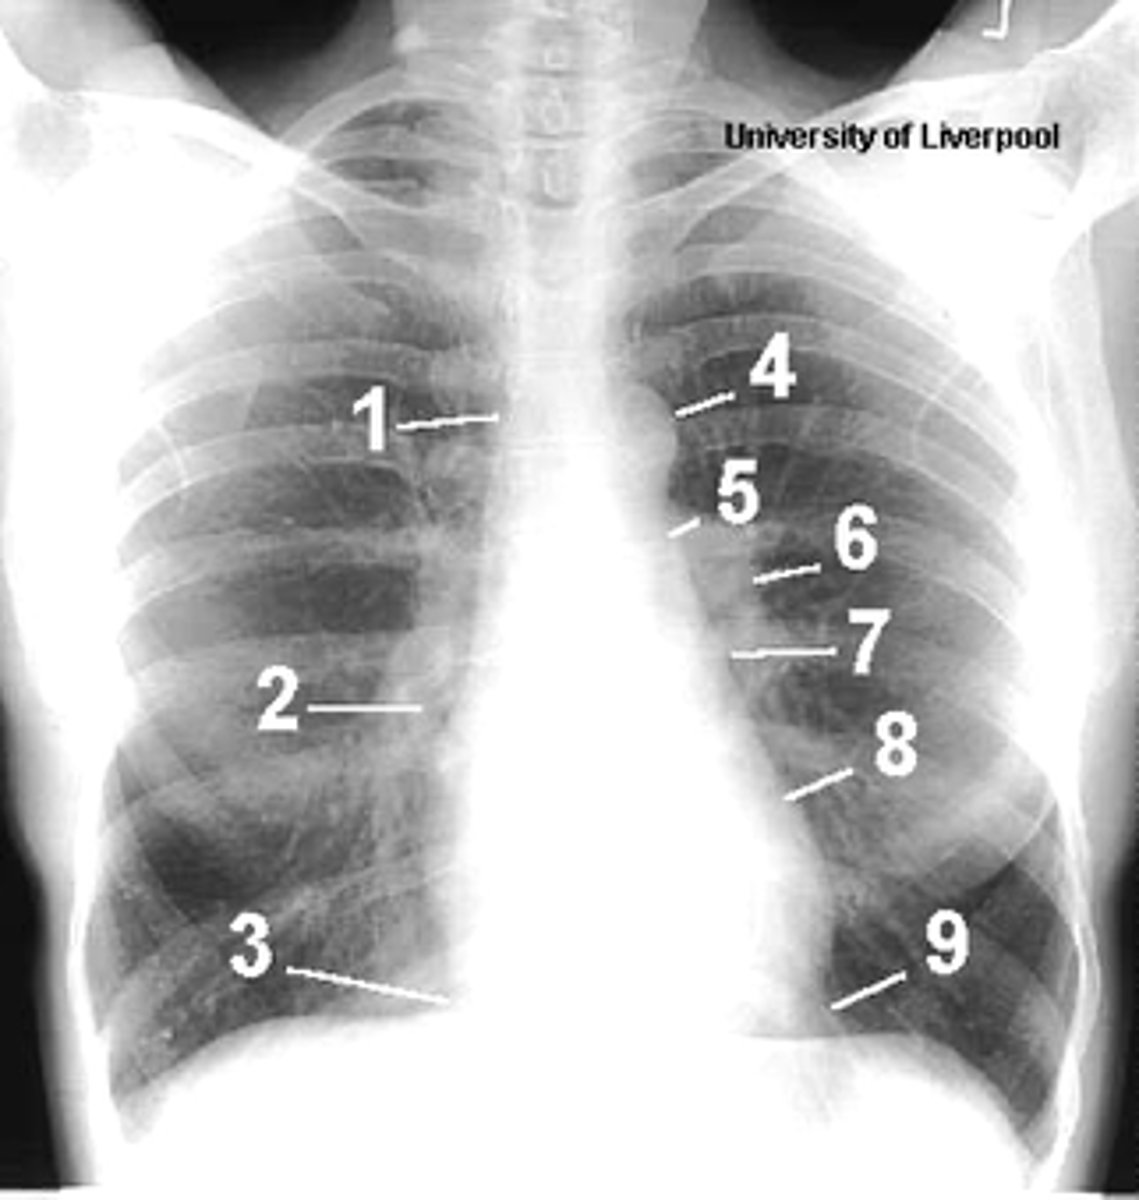

1

superior vena cava

2

right atrium

3

inferior vena cava

4

aortic arch or knob

5

left pulmonary trunk

6

left pulmonary artery

7

left atrium

8

left ventricle

9

left cardiophrenic angle